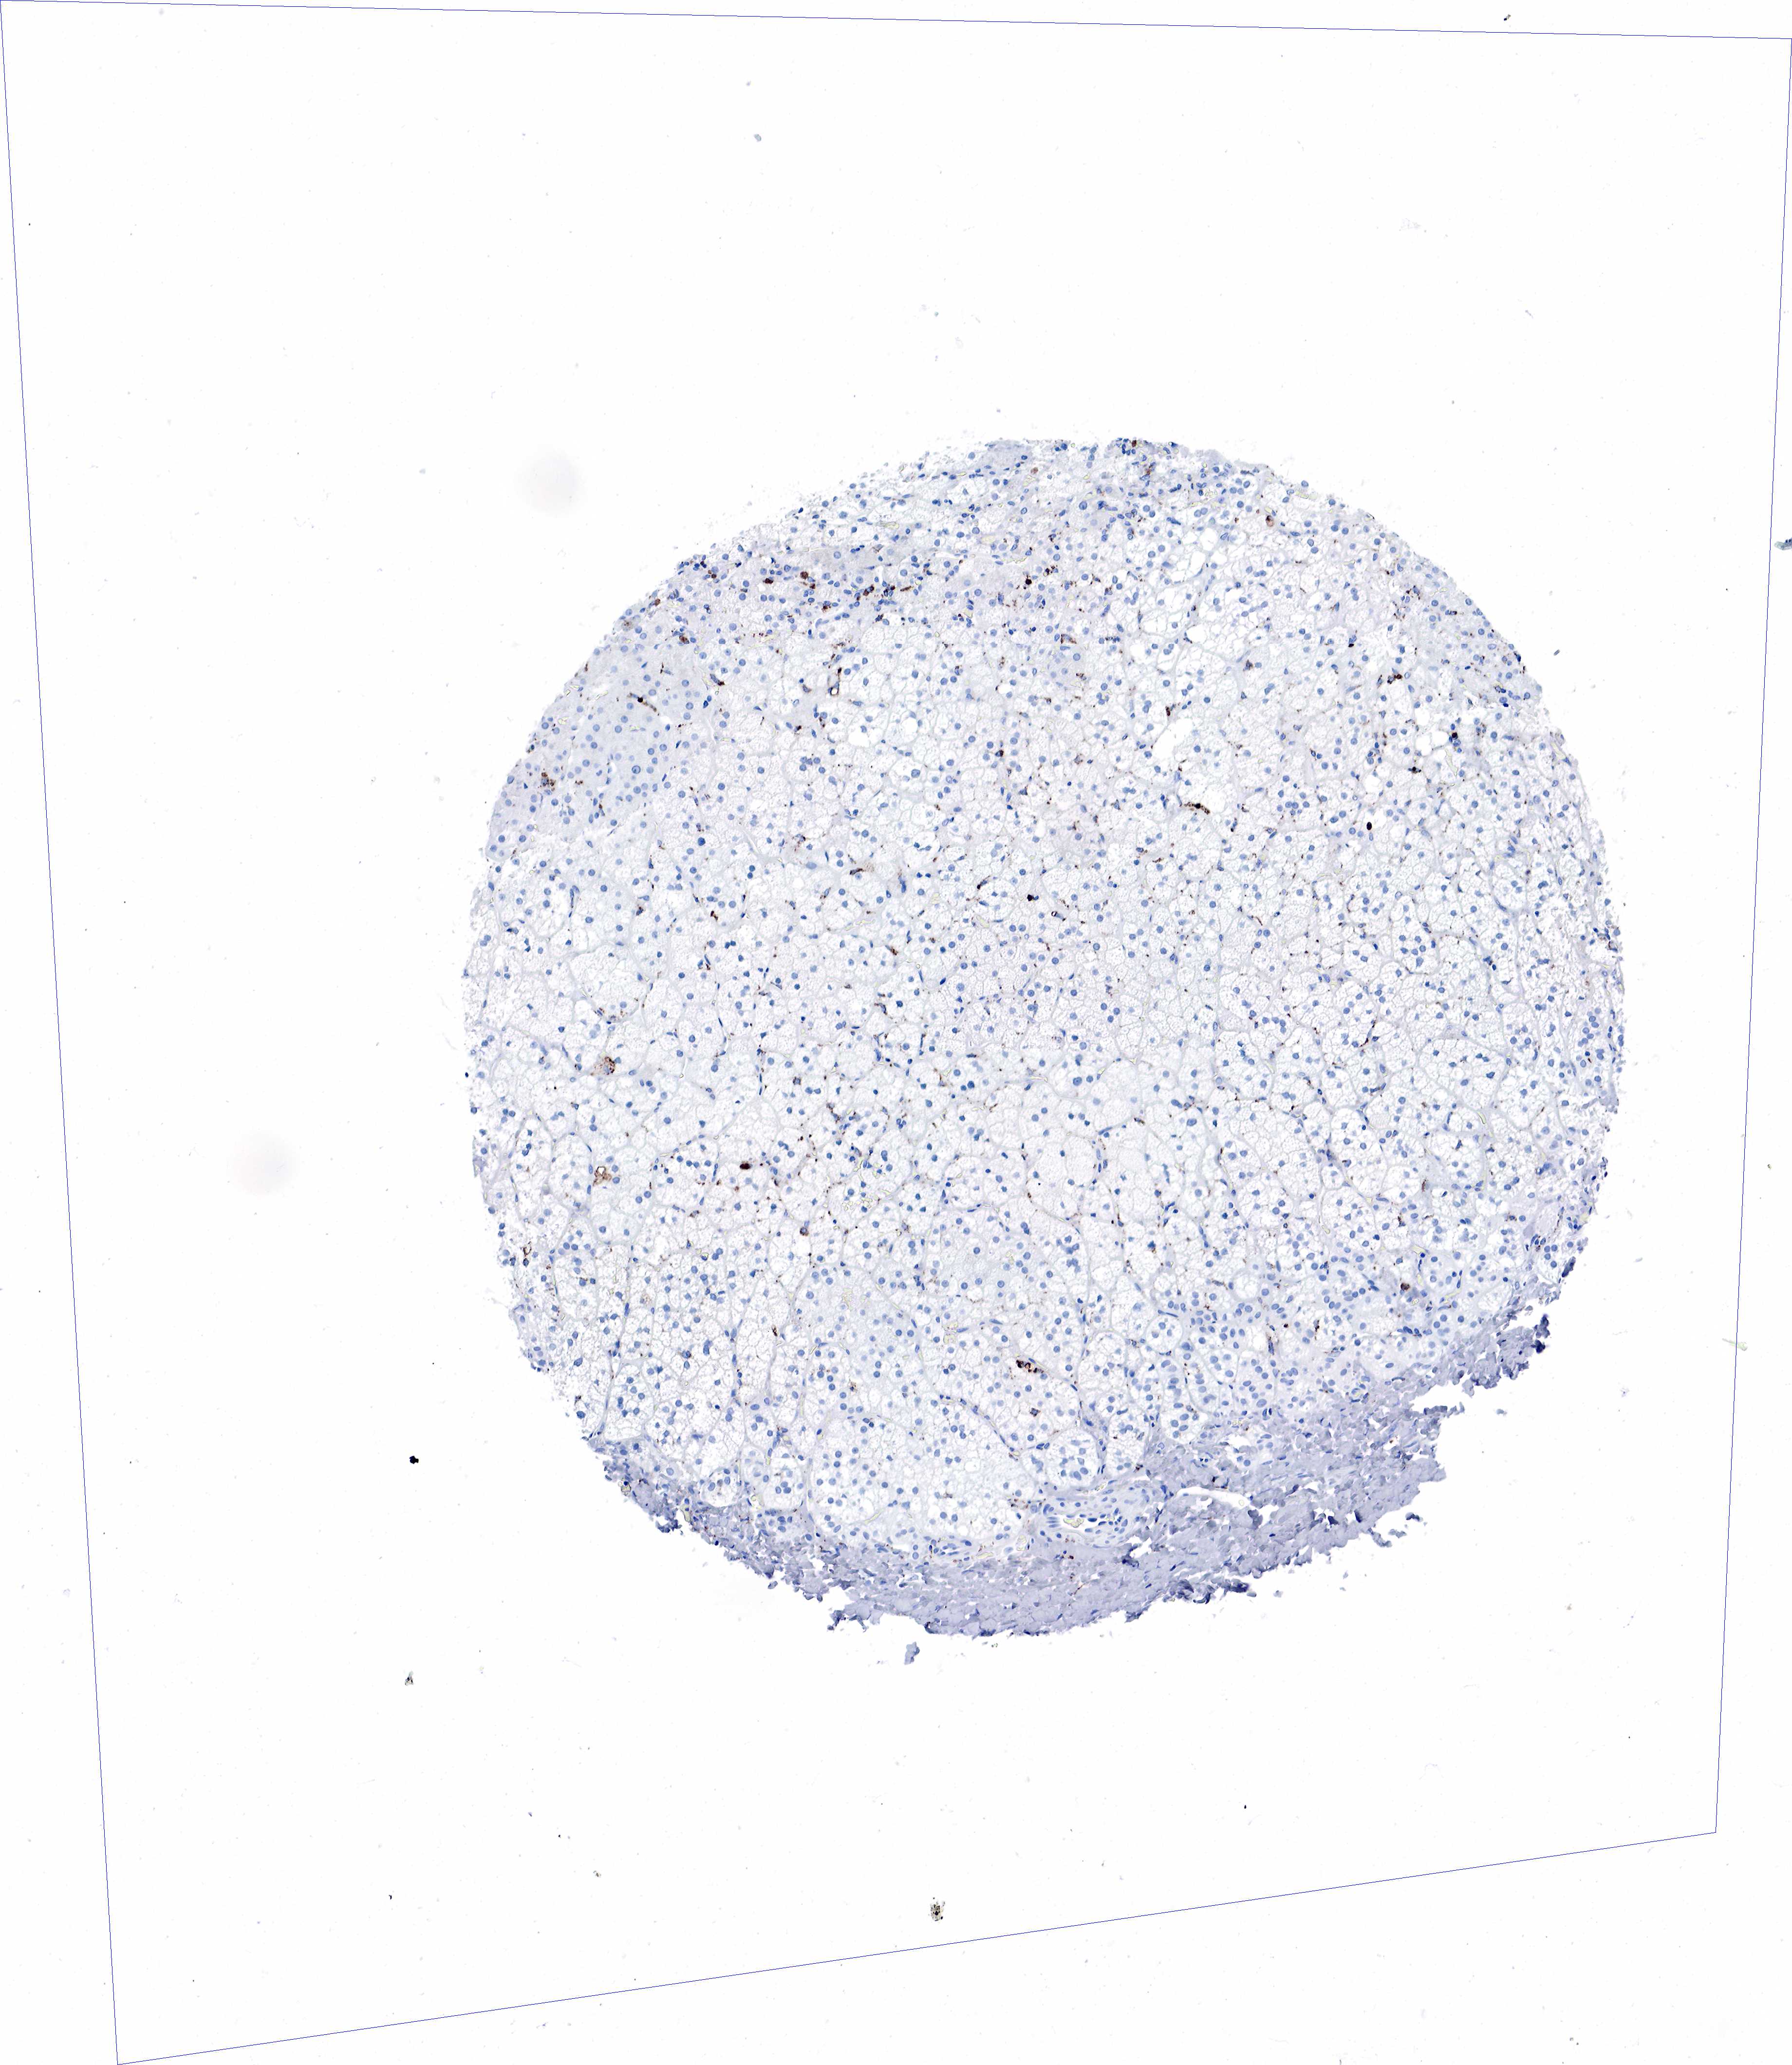

ADRENAL GLAND - Antibody stainingi

Antibody staining in the annotated cell types in the current human tissue is reported as not detected, low, medium, or high, based on conventional immunohistochemistry profiling in selected tissues. This score is based on the combination of the staining intensity and fraction of stained cells.

Each image is clickable and will lead to virtual microscopy that enables deeper exploration of all samples and also displays staining intensity scores, fraction scores and subcellular localization as well as patient and tissue information for each sample.

Antibody HPA048982Antibody CAB000051Antibody CAB000066Antibody CAB072861Antibody CAB072862

Glandular cells Not detectedNot detectedNot detectedNot detectedNot detected